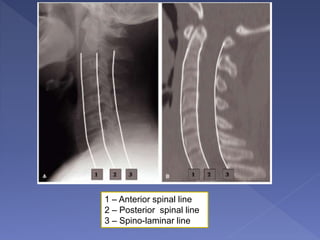

1 – Anterior spinal line

2 – Posterior spinal line

3 – Spino-laminar line